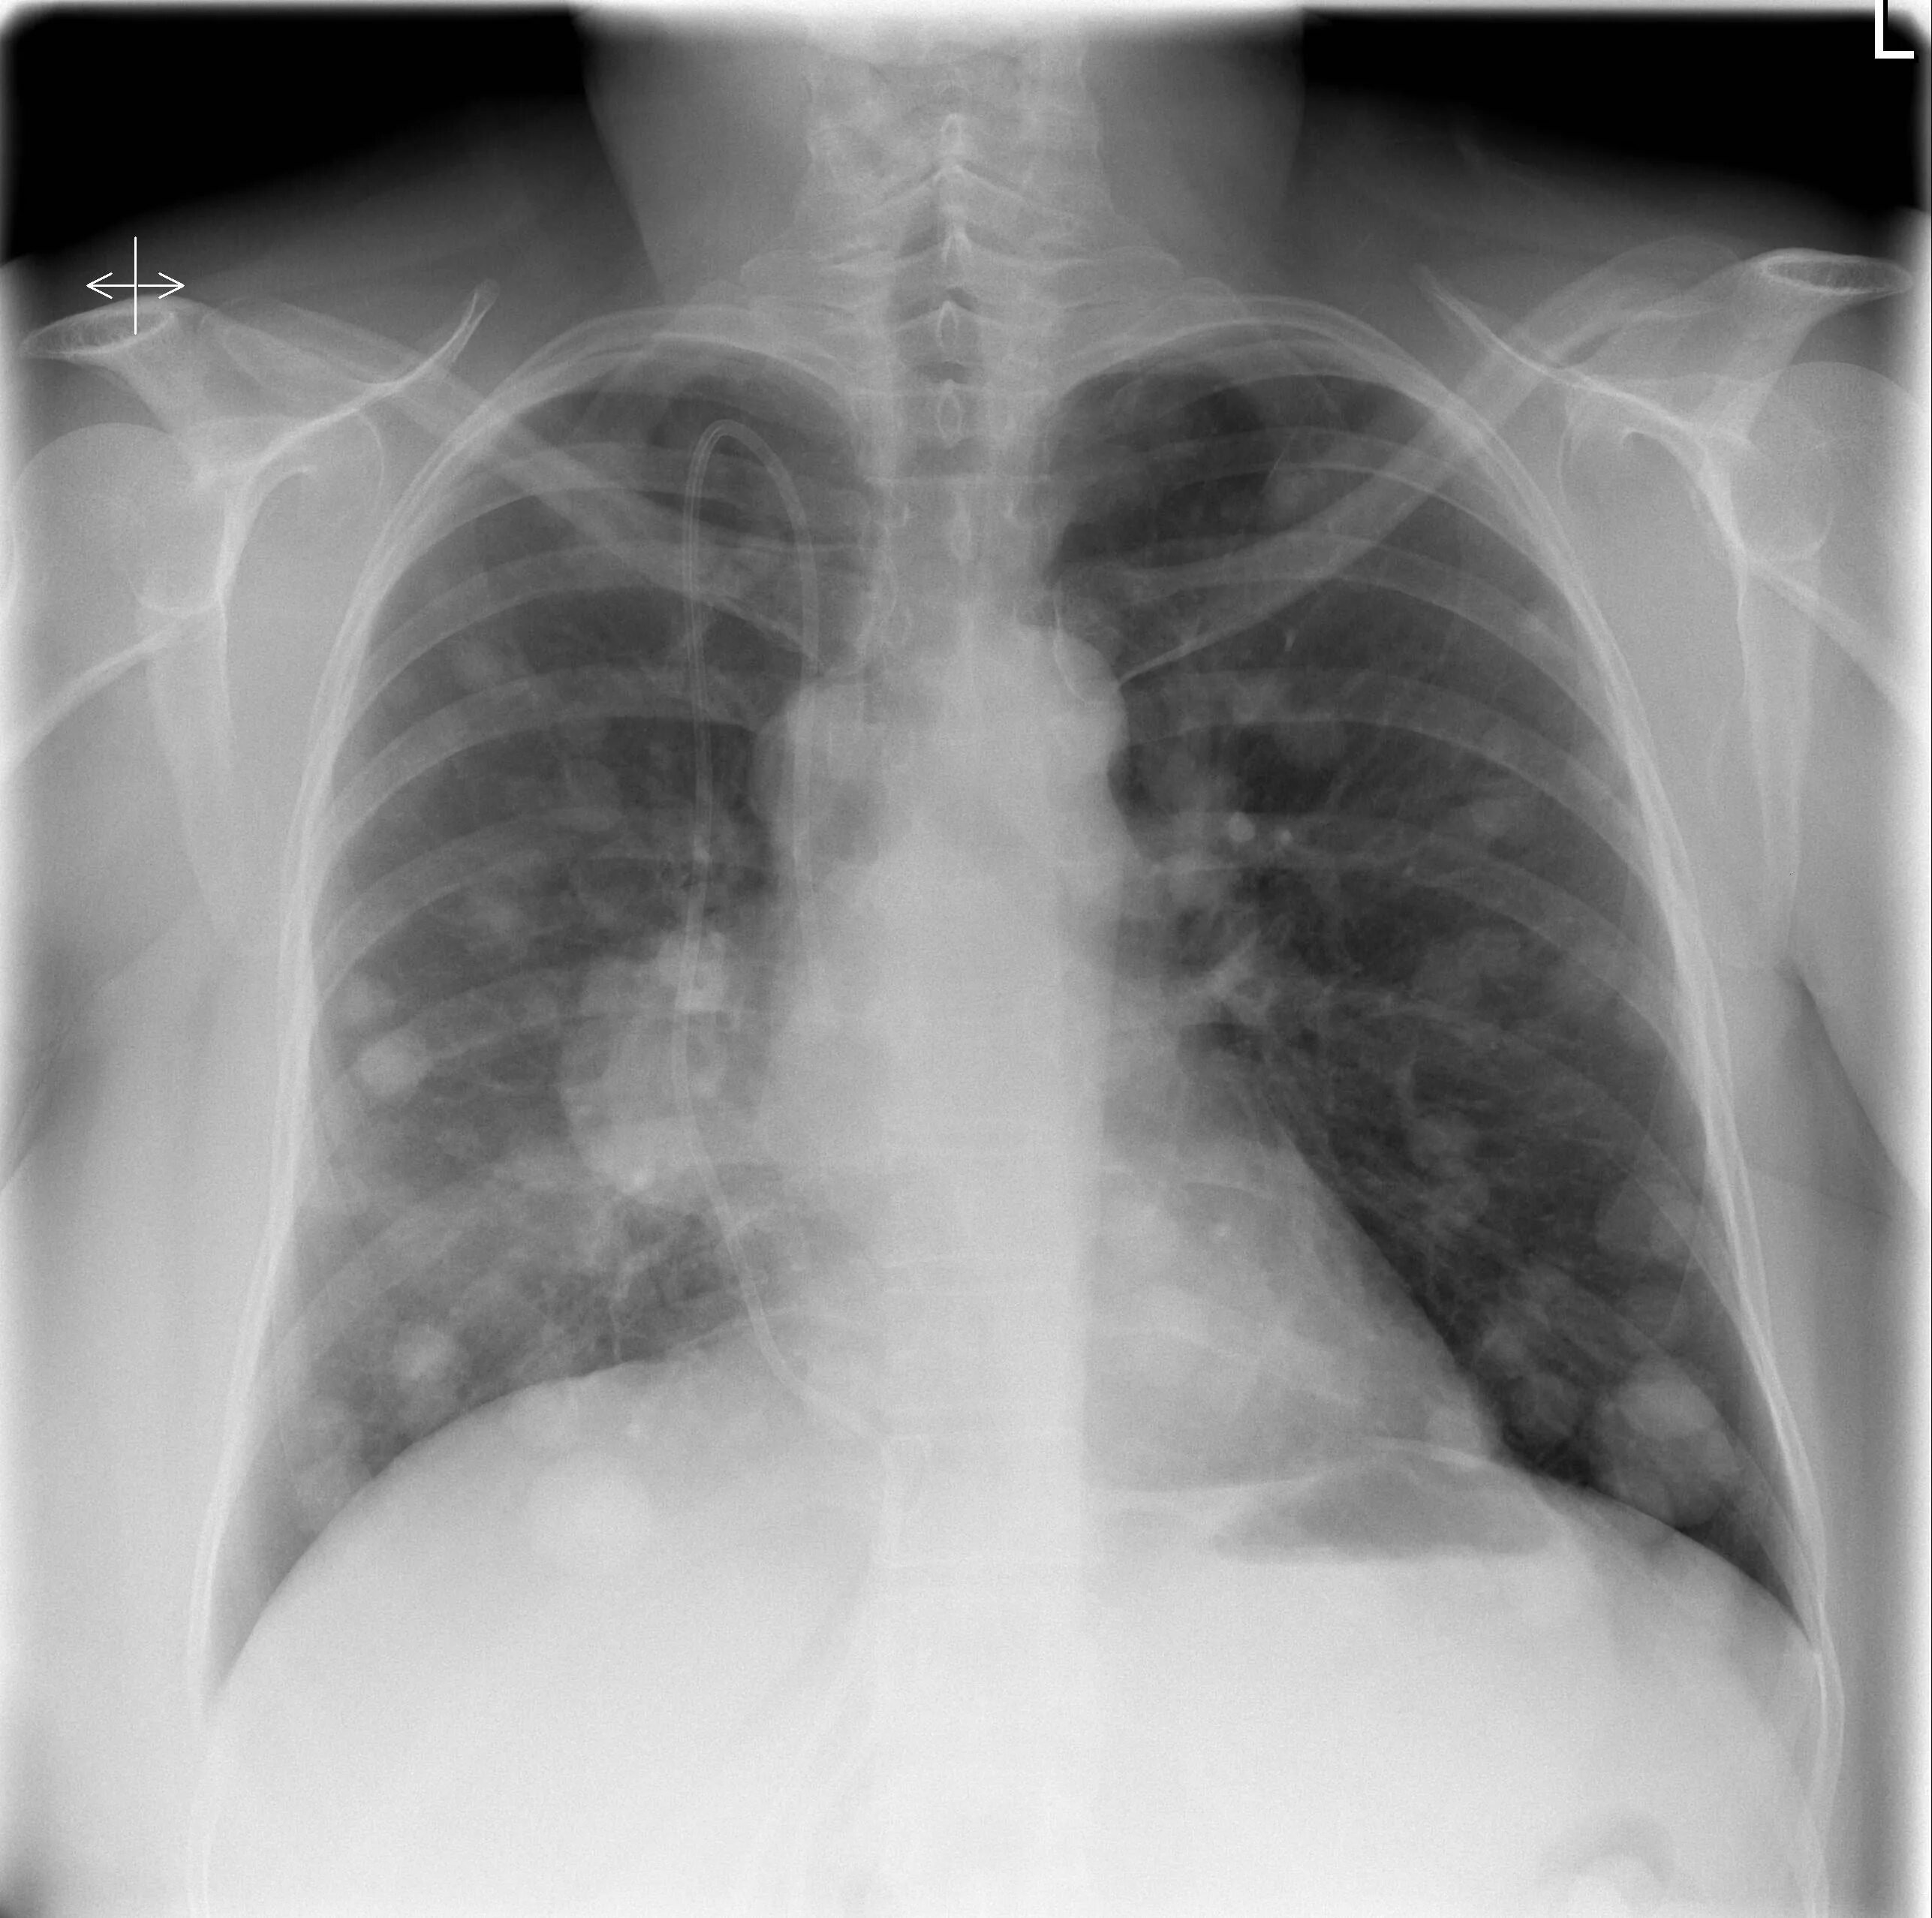

Метастазы в легких терапия